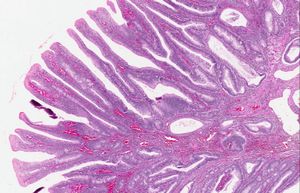

창자의 신생물성 폴립은 흔히 양성이므로 선종이라고 불린다. 선종은 암의 특성을 (아직) 얻지 못한 샘 조직의 종양이다. 대장의 흔한 선종(대장 선종)은 관상, 융모상 관상, 융모상, 무경 유경(SSA)이다.[18] 대다수(65–80%)는 양성 관상 형이며, 10–25%는 융모상 관상, 융모상은 5–10%로 가장 드물다.[9]

융모상 세분은 일반적으로 가장 큰 표면적을 가지기 때문에 가장 높은 악성 잠재력과 관련이 있다. (융모가 루멘으로 돌출되어 표면적이 더 크기 때문이다.) 그러나 융모상 선종은 크기가 모두 동일하다면 관상 또는 융모상 관상 선종보다 암으로 발전할 가능성이 더 높지 않다.[18]